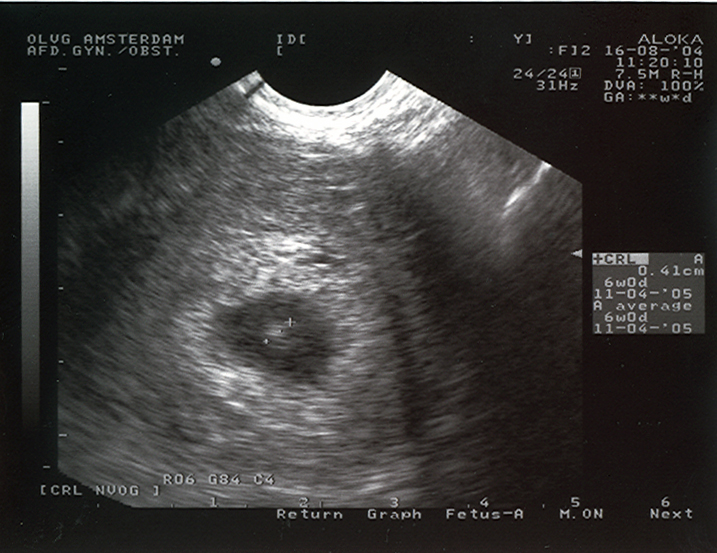

Ultrasound at 28 days

Ultrasound picture of a 4-week old  pregnancy. On the right you can read the size: 0,41 cm. This means that the mother is about 12 days over time. If a pregnancy like this is unwanted, we can end it on our ship when outside the 12 mile zone.